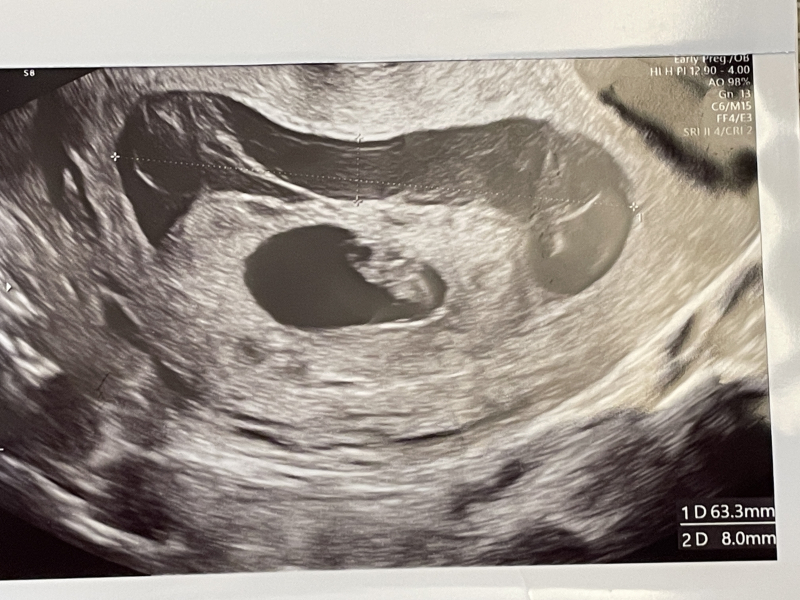

昨日の検診で、血腫は6.3cm✖️0.8cmまで大きくなっており、赤ちゃんを囲むように広がっていました。ネットで絨毛膜下血腫を検索すると、大きい場合は入院や自宅での絶対安静による管理が必要であると書いてありました。担当医からはこのまま血腫が拡大すれば流産の可能性もあると示唆されたものの、入院などは必要なく、日常生活を送ってよい、また現状血腫に対してできることはなく祈るだけ、と言われました。